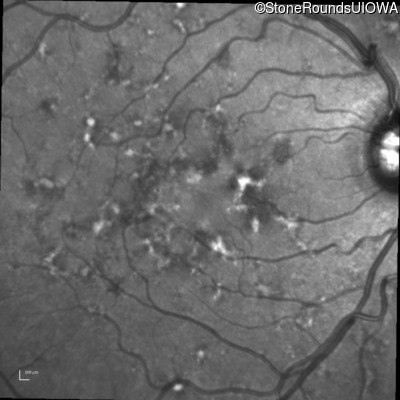

Visit at age: 39 years

Blue Autofluorescence - Left - 20/20 -3

Exemplar